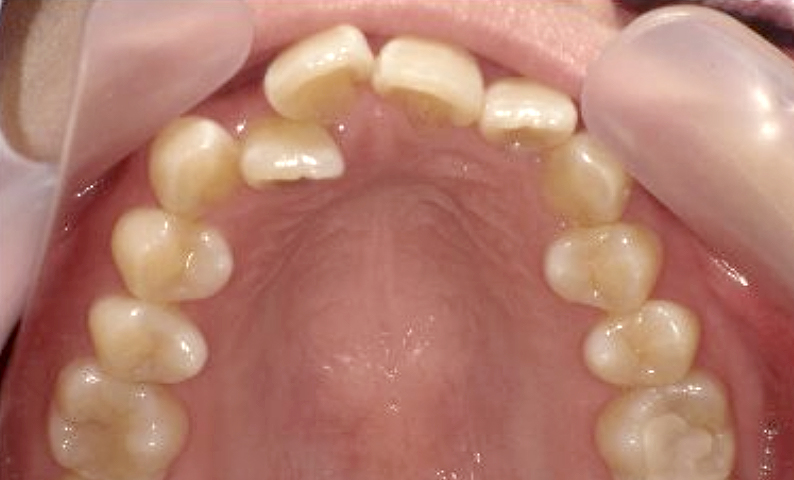

症例_011 上顎だけの部分矯正

治療期間:7ヶ月金額:30万円+税女性八重歯上の前歯だけ

| Before | After |